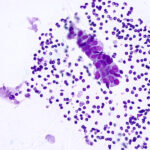

No Cross Contamination

Fresh stains consistently delivered to every slide removing the need for stain filtration. A closed, hands-free design reduces aerosolization and prevents contaminants from migrating between samples.